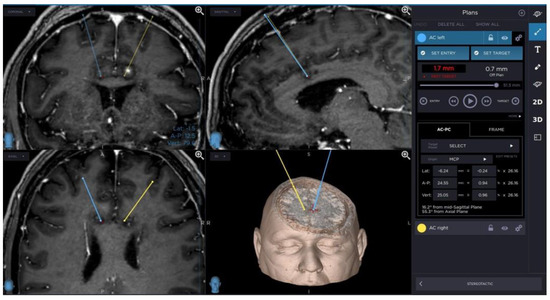

A planning of cingulotomy procedure is presented in Figure 1.

Figure 1. Planning of cingulotomy procedure.